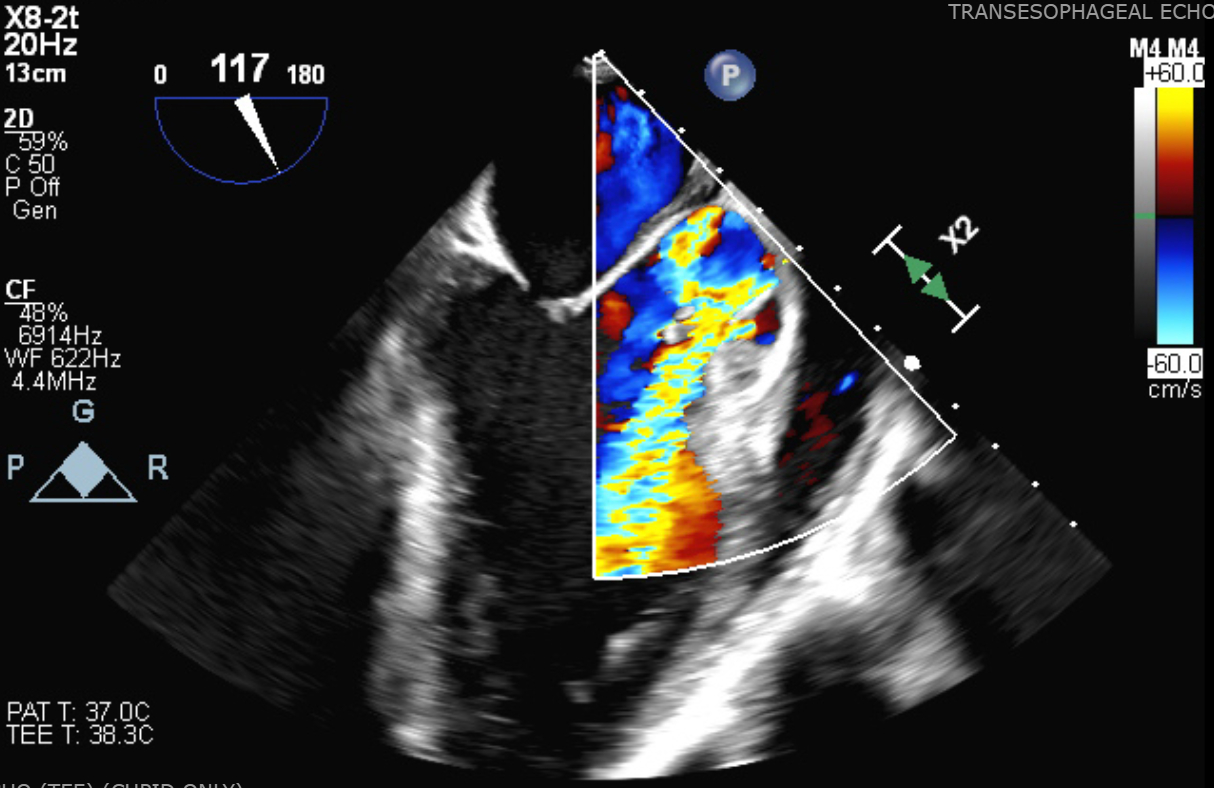

Transthoracic echocardiography (TTE) showed an ejection fraction of 58% with a mobile echodensity on the aortic valve, severe aortic regurgitation, and holo-diastolic flow reversal in the descending aorta. Transesophageal echocardiography (TEE) confirmed a 1.4 × 0.8 cm mobile echogenic mass consistent with vegetation, and an abscess in the right coronary part of the aortic annulus. The patient was started on broad-spectrum antibiotics, including vancomycin and ampicillin-sulbactam.